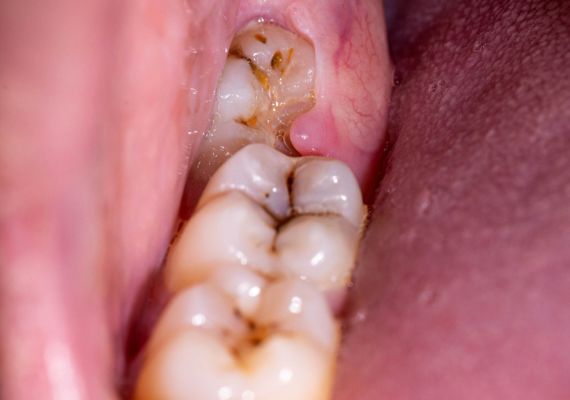

Types of impacted teeth

While all of your teeth can become impacted, there are a few that tend to be the most likely to have complications. Here is an explanation of the different types of impacted teeth:

Other teeth: All of your teeth can become impacted if your dental health isn't paid attention to. Molars, for example, due to their position in the mouth, can become impacted as they erupt.